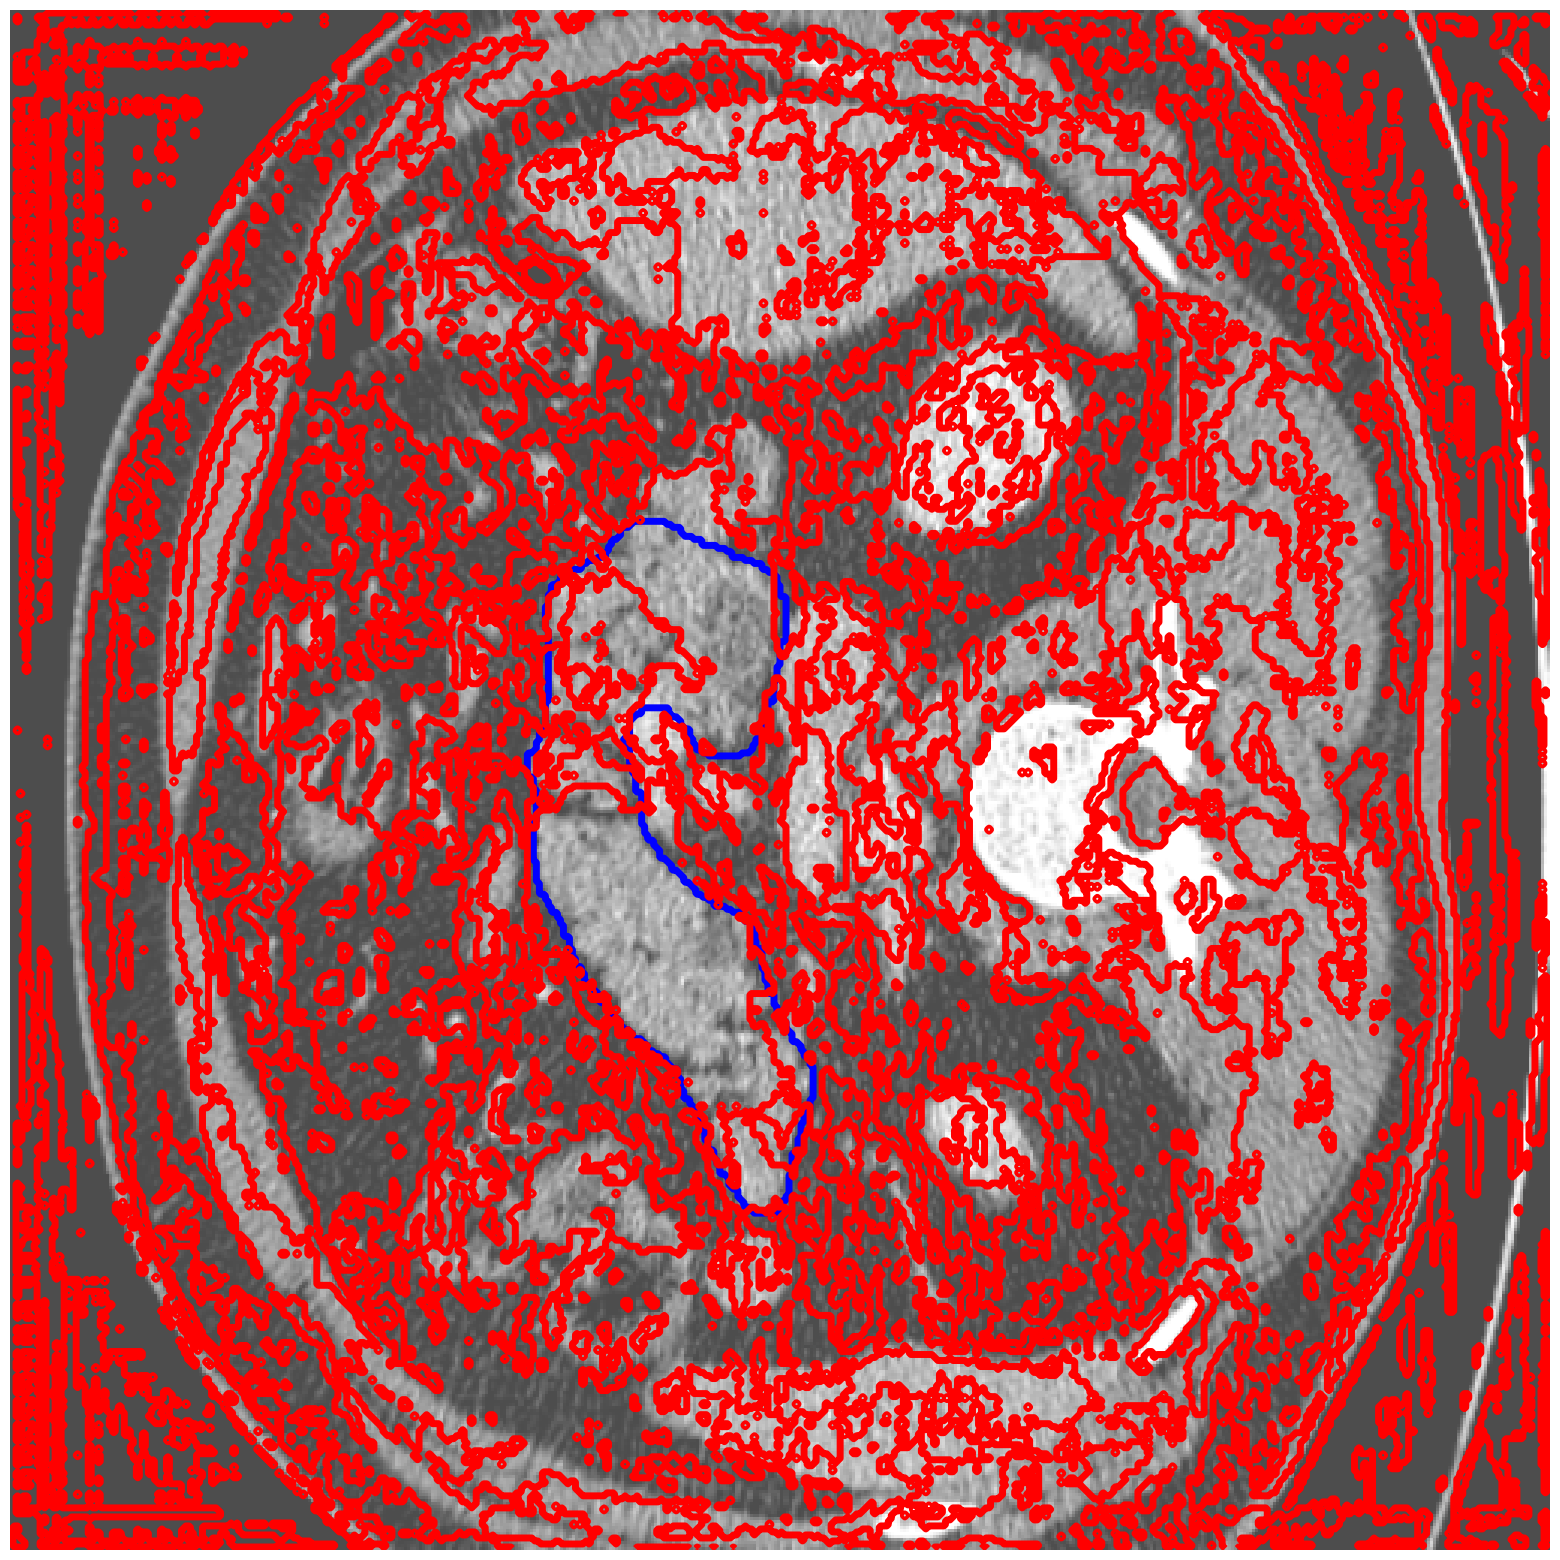

MSD-Pancreas |

![]() |

| (a) Original pred. | b) Consema | ——— c) Standard CRC ——— | ——— d) RW-CP (Ours) ——— | |||

Visually, we observe in Fig. 1 that RW-CP is able to produce prediction sets much closer to the ground-truth than standard CRC or Consema. Our approach is even able to remove small over-segmentated areas, whereas methods such as Consema can only increase the size of the prediction set, even when the segmentation model produced false positives.

We hypothesize that the performance of RW-CP stems from its pre-processing step on probabilities, which mitigates the overconfidence commonly observed in deep learning segmentation models [16]. Their raw softmax probabilities are often skewed towards either 0 or 1 (see Fig. 1.c). This overconfidence compresses the effective range of possible values for the empirical threshold used in Conformal Risk Control, making the final prediction mask extremely sensitive to small fluctuations in . On the contrary, by first applying a diffusion process, the pixel-wise probabilities become more varied and less polarized (as shown in Fig. 1.d). This broadened distribution stabilizes the empirical during calibration, leading to a more robust and tighter prediction set, which translates to better overall segmentation metrics